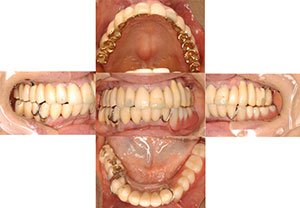

16年後全てのインプラント安定してます

初診時

治療後

【症例2 37歳 男性 上顎前歯疼痛】

| 治療内容 | 主訴:強度の嘔吐反応があり、義歯を入れる事が出来ないため、当院へご相談しに来院されました。 処置:重度の歯周病のため、上顎は全て歯を抜歯して、10本のインプラント治療を、科学は歯周外科手術を行った後に3本のインプラント埋入して噛めるようにする治療計画を立てました。上顎両側の骨幅が足りないので、スプリットクレスト法(歯槽骨頂分割術)を用いて、インプラント(人工歯根)を埋める一次手術を行いました。その後、上顎の二次手術と下顎右側臼歯部の人工歯根を埋める一次手術を同時に行いました。義歯を入れる事が出来なかった患者様でしたが、「ちゃんと噛めて夢のようです。」と感動されました。定期的にメンテナンスにもこられ、16年後も全てインプラントが安定されております。 |